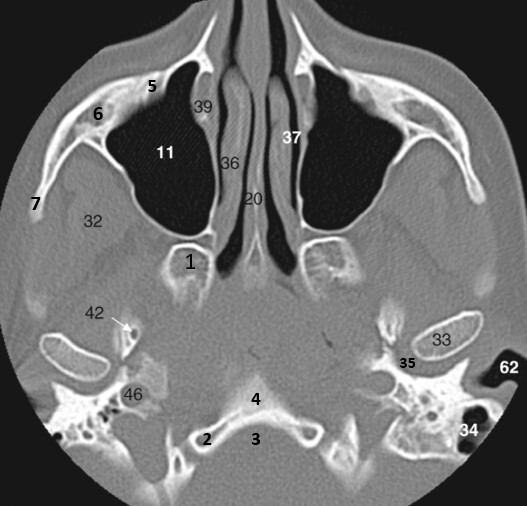

1

Label 5,6,10,11,12

5-Rt masseter muscle

6-Rt ramus of mandible

10=Median suture (hard palate)

11=Rt maxillary sinus

12=Rt Maxilla

2

Label 13-18

13=Lt lateral pterygoid process (Sphenoid)

14=Lt. medial pterygoid process (Sphenoid)

15=Horizontal plate (Rt palatine)

16=Nasopharynx

18=Odontoid process of C2

19

Label 7,20,32,33,34

7=Rt Zygomatic arch

20=Nasal septum (Vomer)

32=Right Temporalis muscle

33=Lt condyloid process (mandible)

34=Left Mastoid air cells